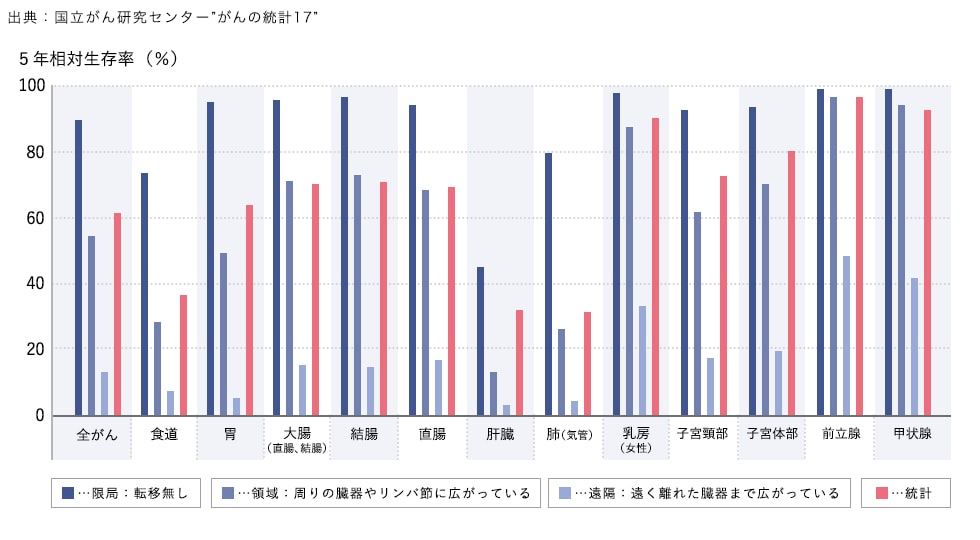

進行度別に見た各部位のがんの5年生存率

多くのがんにおいて90%近い患者様が診断後5年経っても生存しているという結果に対し、領域転移、遠隔転移するにつれて、5年生存率は下がっています。